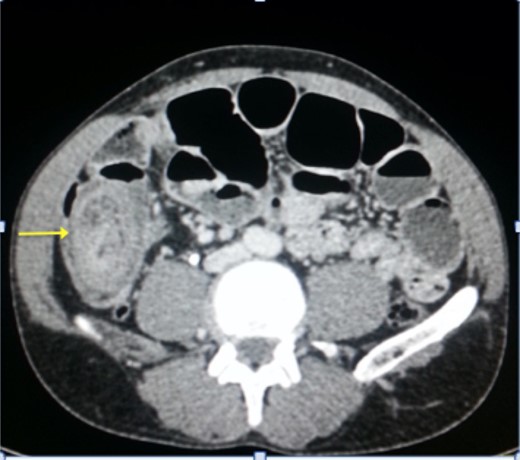

The post-operative outcomes were favorable. The pathological examination of the surgical specimen found an adenomatous ileal polyp with a high grade dysplasia on the terminal ileum being the cause of the ileocecal intussusception (Fig. 4).